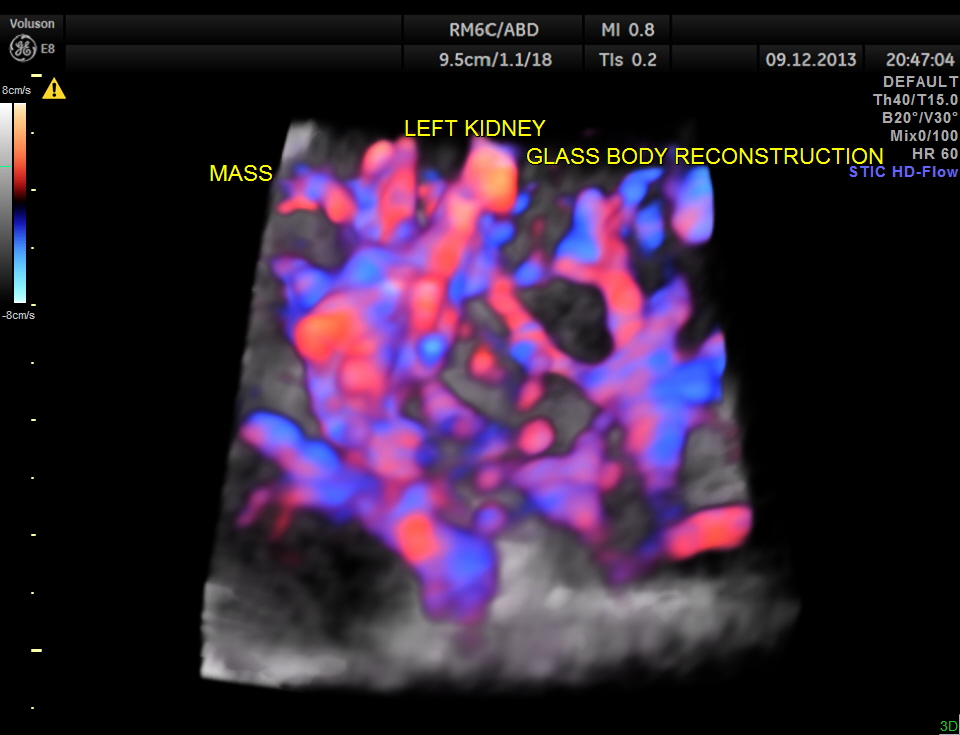

GLASS BODY RECONSTRUCTION IS GIVEN BELOW.

INCREASED VASCULARITY OF THE MASS IS WELL MADE OUT IN THIS GLASS BODY RECONSTRUCTION.

COLOUR FLOW ONLY RECONSTRUCTION.